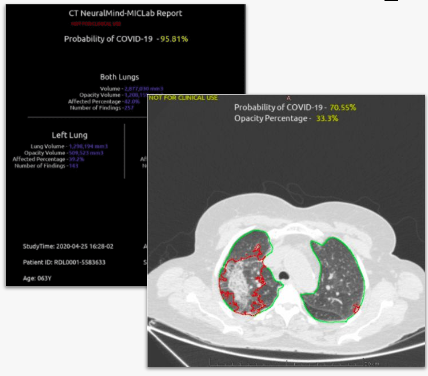

Algoritmos para análise de TC e RX para detecção de COVID-19, integrados à plataforma RadVid19.